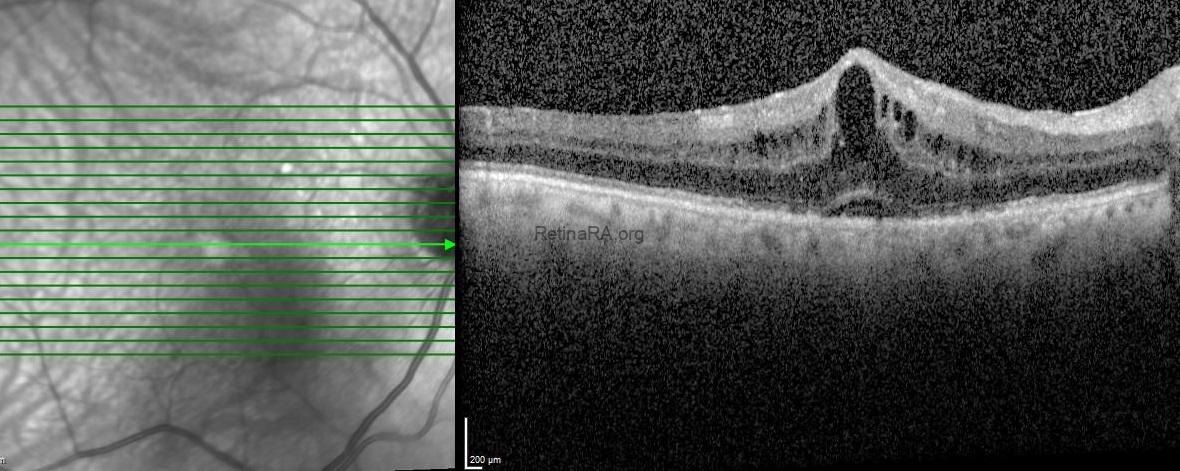

Optical coherence tomography (OCT) exhibited retinal thickening, intraretinal cystic spaces and serous retinal detachment in the right eye and subretinal drusenoid deposits and drusenoid pigment epithelium detachment with normal foveal contour in the left eye.

The patient was diagnosed as pseudophakic cystoid macular edema also known as Irvine-Gass syndrome and topical nepafenac 0.1% eye drops

3 times per day was recommended. One-month after the topical treatment, the BCVA of the right eye improved to 20/25 and OCT showed the complete resolution of subretinal and intraretinal fluid.